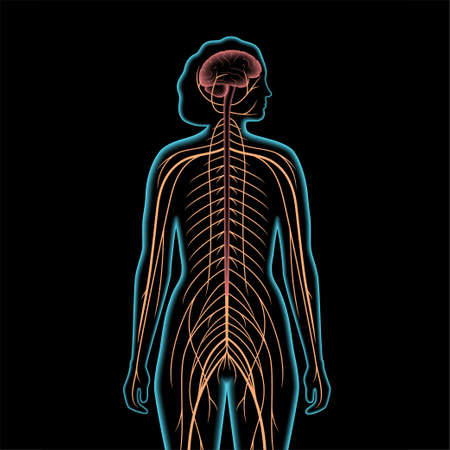

Illustrating the role of the central nervous system in processing sensory information and coordinating motor responses.

A captivating digital depiction of the human nervous system, highlighting the brain and spinal cord with glowing neural connections, perfect for educational materials.

human nerve pathways run through the entire body

Human body in transparent glass isolated on black background. Skeleton and nerve treads, including brain

human nerve pathways run through the entire body

Human nervous system diagram, centrally aligned with plenty of blank space around for copy. -

A detailed anatomical diagram of the human nervous system, highlighting the brain, spinal cord, and peripheral nerves, arranged for educational clarity

This artistic visualization depicts the human anatomy, highlighting the brain, spine, and nervous system in vibrant red hues. Aimed at educational and medical audiences, this model enhances comprehension of human physiology.

human nerve pathways run through the entire body

human nervous system.

Central nervous system

human nerve pathways run through the entire body

Human nervous system. Sympathetic and parasympathetic nerves anatomy and functions. Spinal cord controls body internal organs vector diagram

Detailed anatomical illustration depicting the human spine and nervous system connected to the brain, suitable for educational materials in health and science fields.

human nerve pathways run through the entire body